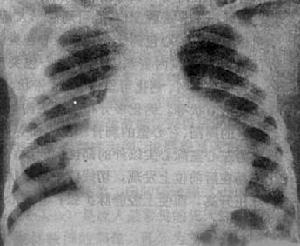

臨床多通過常規X線胸片檢查發現心影增大,再經UCG和全身系統檢查,以及病因學檢查,排除特異性病變如結核性心包炎、風濕性心包炎等之後可診斷本病。

心包積液常見症狀為發熱,胸痛,咳嗽和呼吸困難。心包填塞或縮窄性心包炎則可出現外周靜脈搏血循環壓力增高表現,如下肢水腫、腹水等。體徵為心濁音界增大,心音遙遠,心包摩擦音,心動過速等。部分病人臨床表現並不典型,起病隱匿,無結核中毒症狀。診斷主要根據臨床表現,心包積液檢查及結核病史。心包積液中結核菌檢查和培養陽性的檢出率不高,OT試驗也僅60%患者為中等度陽性或強陽性。心包積液培養需4~6周,心包活檢較難實施。近來開展的PCR檢查可提高診斷陽性率。超聲心動圖檢查是非特異性的,但能確定心包積液的量、心包粘邊或增厚,為病因診斷提供有價值的參考資料,同時能評估療效。X線胸片可見心臟向兩側擴大,心電圖可有QRS波群低電壓和T波倒置。部分患者需根據治療結果進行治療性診斷。近年磁共振成像技術也可為了解心包積液的程度提供依據。